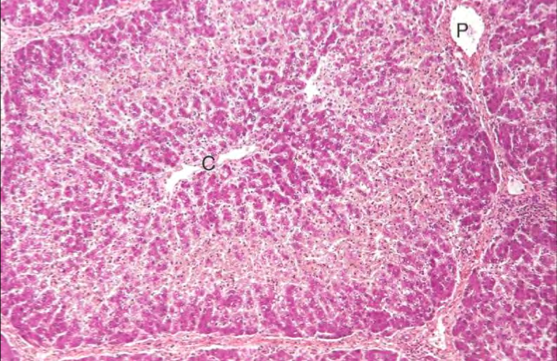

Centrilobular or Zone 3/ periacinar or Centrilobullar necrosis is commonly due to hypoxia. Pig liver. C = central vein

Midzonal necrosis. Pig liver. C = central vein, P = portal area. This pattern of degeneration and necrosis is rarely seen.